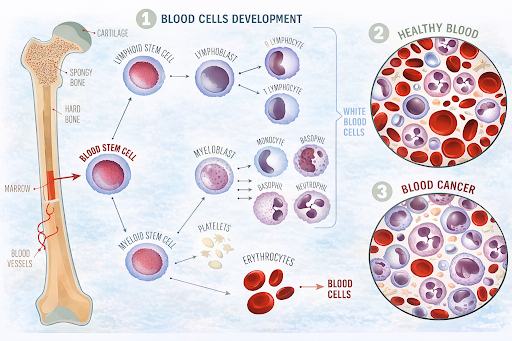

Overview

What are Blood Cancers and Lymphomas?

Blood cancers are a group of cancers that affect the blood, bone marrow, or lymphatic system. Lymphomas are a type of blood cancer that primarily involves the lymphatic system, which plays an important role in immunity. These cancers occur when certain blood-forming or immune cells begin to grow and behave abnormally.

Blood cancers are a group of cancers that affect the blood, bone marrow, or lymphatic system. Lymphomas are a type of blood cancer that primarily involves the lymphatic system, which plays an important role in immunity. These cancers occur when certain blood-forming or immune cells begin to grow and behave abnormally.

Where It Begins

Blood cancers and lymphomas may begin in:

Because these systems are interconnected, abnormal cells may circulate or appear in multiple areas.

- Bone marrow, where blood cells are produced

- Bloodstream, which carries cells throughout the body

- Lymphatic system, including lymph nodes, spleen, thymus, and lymph vessels

Because these systems are interconnected, abnormal cells may circulate or appear in multiple areas.

Who Can Be Affected

Blood cancers and lymphomas may be seen in:

- Both children and adults, depending on the subtype

- Slightly higher rates in older adults for many forms

- All genders, with some subtypes being more common in one gender

- People with certain immune-related or genetic conditions

How does it develop?

These cancers typically develop when blood or immune cells undergo genetic changes that alter their growth and division. Instead of maturing normally, these cells may multiply uncontrollably and fail to function properly. Over time, they can crowd out healthy cells or interfere with normal immune responses.

Leukaemia: Types and Staging

Types of Leukaemia

Leukaemia is commonly grouped based on how quickly it develops and the type of blood cell involved.

Acute Leukaemia

Develops rapidly and involves immature blood cells. Symptoms often appear suddenly and require prompt medical attention.

Chronic Leukaemia

Develops more slowly and involves more mature blood cells. Some people may have few or no symptoms initially.

Leukaemia is also classified by the blood cell affected:

Staging of Leukaemia

Leukaemia is not staged like solid tumors. Instead, doctors assess:

Lymphoma: Types and Staging

Types of Lymphoma

There are two main types:

Hodgkin Lymphoma

Characterised by the presence of a specific abnormal cell type.

Non-Hodgkin Lymphoma

A larger group with many subtypes that vary in how they grow and respond to treatment.

Lymphomas may also be described as:

Staging of Lymphoma

Lymphoma is staged based on how far it has spread within the body:

Leukaemia: Types and Staging

Types of Leukaemia

Leukaemia is commonly grouped based on how quickly it develops and the type of blood cell involved.

Acute Leukaemia

Develops rapidly and involves immature blood cells. Symptoms often appear suddenly and require prompt medical attention.

Chronic Leukaemia

Develops more slowly and involves more mature blood cells. Some people may have few or no symptoms initially.

Leukaemia is also classified by the blood cell affected:

- Lymphocytic Leukaemia – affects lymphocytes

- Myeloid Leukaemia – affects myeloid cells

Staging of Leukaemia

Leukaemia is not staged like solid tumors. Instead, doctors assess:

- Blood and bone marrow test results

- The number of abnormal cells

- Effects on organs such as the lymph nodes, liver, or spleen

Lymphoma: Types and Staging

Types of Lymphoma

There are two main types:

Hodgkin Lymphoma

Characterised by the presence of a specific abnormal cell type.

Non-Hodgkin Lymphoma

A larger group with many subtypes that vary in how they grow and respond to treatment.

Lymphomas may also be described as:

- Slow-growing (indolent)

- Fast-growing (aggressive)

Staging of Lymphoma

Lymphoma is staged based on how far it has spread within the body:

- Stage I – Involvement of a single lymph node region or site

- Stage II – Involvement of two or more regions on the same side of the diaphragm

- Stage III – Involvement on both sides of the diaphragm

- Stage IV – Spread to organs outside the lymphatic system

Possible Risk Factors

Several factors may increase the risk of blood cancers and lymphomas, including:

- Certain genetic conditions or family history

- Weakened immune system, including autoimmune diseases

- Previous cancer treatments, such as chemotherapy or radiation

- Exposure to specific chemicals or radiation

- Certain viral infections, such as Epstein–Barr virus (EBV) or HIV